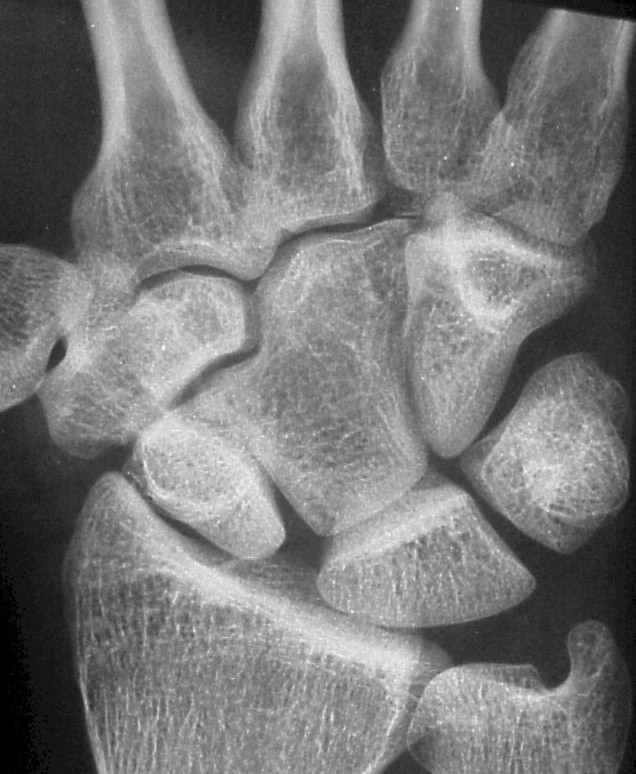

The opposite wrist is similar. This anatomy probably represents congenital carpal coalition between the capitate and an os centrale.